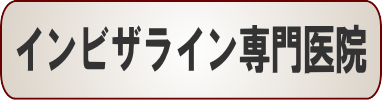

☆出っ歯矯正症例(E.H様 42歳 女性)

主訴は前歯の前突感の改善です。

まずはワイヤーを使用して右上のデコボコを改善していきます。

ワイヤーの使用期間が約3か月で、マウスピースを3か月使用して歯並びを内側に傾斜して治療していきました。

トータルでの治療期間は6ヵ月で、調整料金を含めたトータルの治療費は29万円です。

上側だけの部分矯正では、噛み合わせは変わりませんので、見た目の改善だけの審美治療になります。

部分矯正において、ワイヤーでデコボコを改善するだけだと、矯正前よりも少しだけ前方に出てしまうため、歯の隣接面を少し削ることで前歯の前突感を改善していきます。

どこまで前歯を中に入れたいかで、隣接面を削る量は患者様の判断で決まります。

また歯を削らないでデコボコを治すだけですと、デコボコのある間にブラックトライアングルという隙間も残るため、ブラックトライアングルを減らすという目的のためにも前突感を改善するためにもその部分の隣接面を削って内側へ入れていきます。